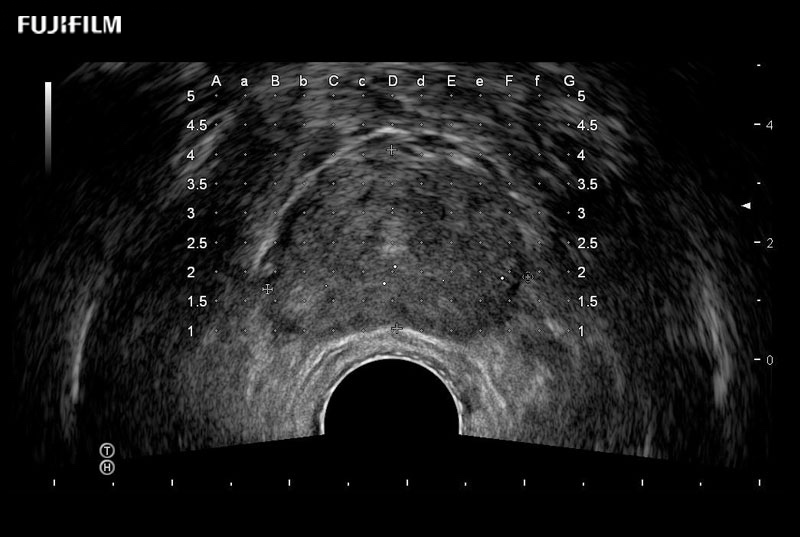

Ideal transducer for Transperineal Biopsy, Hydrogel Spacer Placement, Brachy LDR & HDR, Cryo, and MPMRI procedures.

Main Specifications: